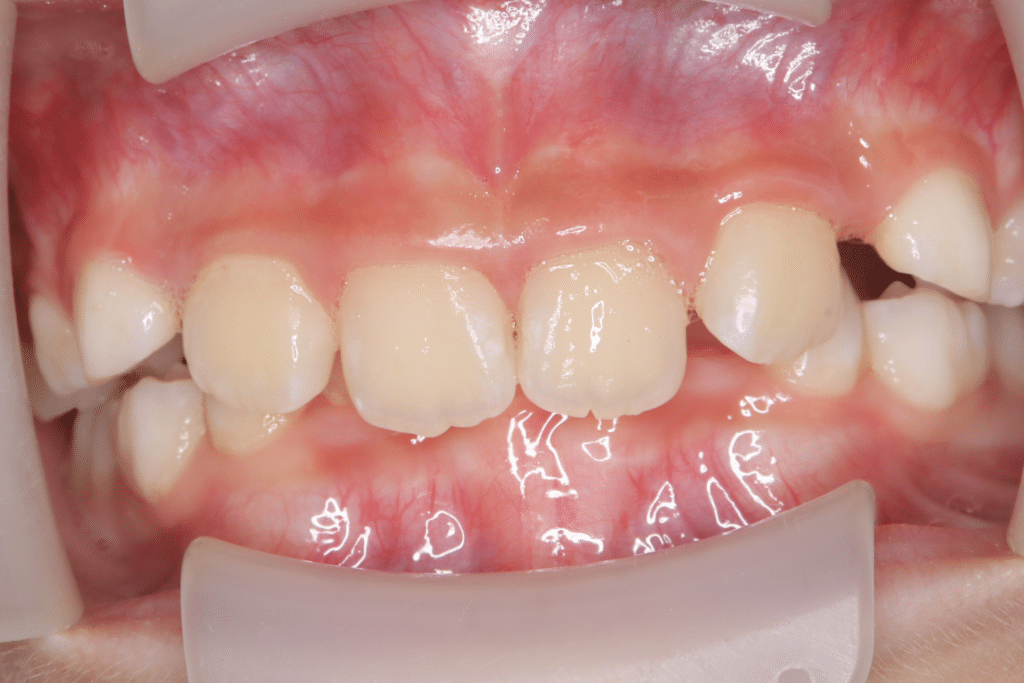

過蓋咬合

(9歳3ヶ月)

開始後1ヶ月